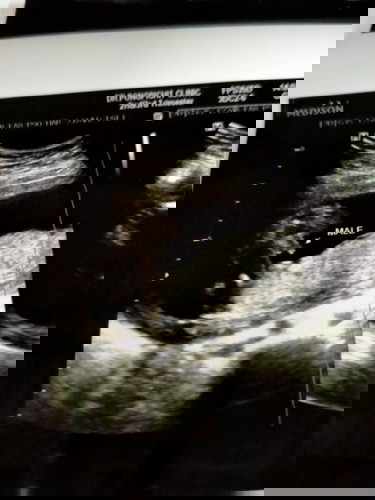

18w 5d ไปซาวด์มาวันนี้เห็นจู๋ชัดเจนเลยคะ เกินคาดมาก ก่อนหน้านี้มีแต่คนทักว่าเป็นผู้หญิง แม่ๆบ้านอื่นรู้เพศกันยังคะ?